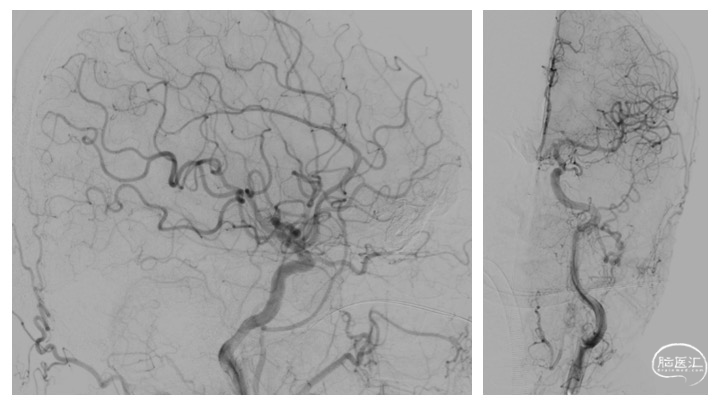

详细分析患者瘘口的血管构筑学(图3),术者认为经静脉途径的优势在于:相对于动脉途径,微导管经静脉途径能够确切地到达瘘口。且该患者的引流虽经皮层及额底内侧静脉分别向矢状窦及直窦引流,但两支引流静脉均起源于一短段的引流静脉。虽然皮层引流静脉有两处走行纤细,但根据术者既往的经验,微导管通过此处并不十分困难。术中同时穿刺右侧股动脉及股静脉,将造影导管超选至右侧颈总动脉,用于实时造影、三维血管构筑分析及路图指导。同时,将Neuronmax长鞘引导至右侧横窦,6F银蛇中间导管引导至上矢状窦中份。在路图指导下,Echelon-10导管经由矢状窦-右侧额叶皮层静脉途径成功超选至右侧额底引流静脉开口,在此处放置弹簧圈,用于防止Onyx逃逸,导致静脉窦栓塞或肺栓塞,随后在静脉端使用逆向高压锅技术,注入Onyx胶,完全栓塞瘘口(图4、5)。

栓塞术后即刻CT未见颅内出血、Onyx胶逃逸或异位栓塞(图6)。次日,患者未诉明显不适,查体无新发神经系统体征。术后第二日,患者顺利出院。